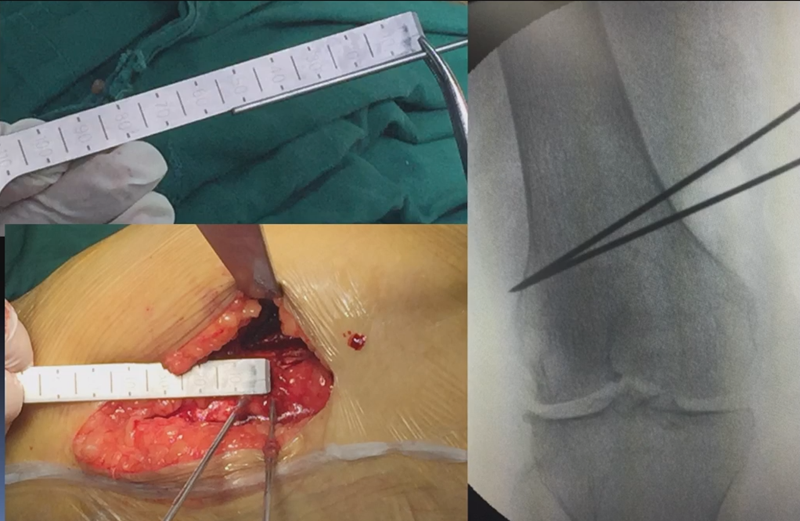

3、选择合页位置和截骨线

合页点的选择与HTO一样,通常需要尽可能接近畸形部位,既要有很好的骨质结构,还要有坚韧的软组织覆盖,以保证稳定性和术后有良好的血运。合页宽度不宜太长,通常保留在5mm。

合页点定位有两种方法,一种为定位在股骨外后髁上缘2mm位置,通常将此区域叫做“鹰嘴区”,以此为解剖标记法来定位合页点。

另一种通过导针从截骨入点向股骨外后髁后缘打出一条切线,此切线与外侧骨皮质的交点,也可作为合页点,这种方法称为导针法。这两种方法在手术之中是可以互为验证的。

合页点处于松质骨区,易形变区,如选择周边区域较脆易折断。另外合页点后方有小腿三头肌的附着点,有很好的的软组织和血运,综合来说作为合页非常合理。

截骨线入点同样也可以采用两种方法选择。一种为钢板标记法,即使用tomfix钢板远近端的无孔区作为截骨入点。

另一种为解剖标记法,在切开显露后可以看到一处恒定血管,即内侧上横动脉,在此附近做截骨即可。如做外侧闭合楔时,同样在外侧也可以看到一处恒定血管,为外侧横动脉。